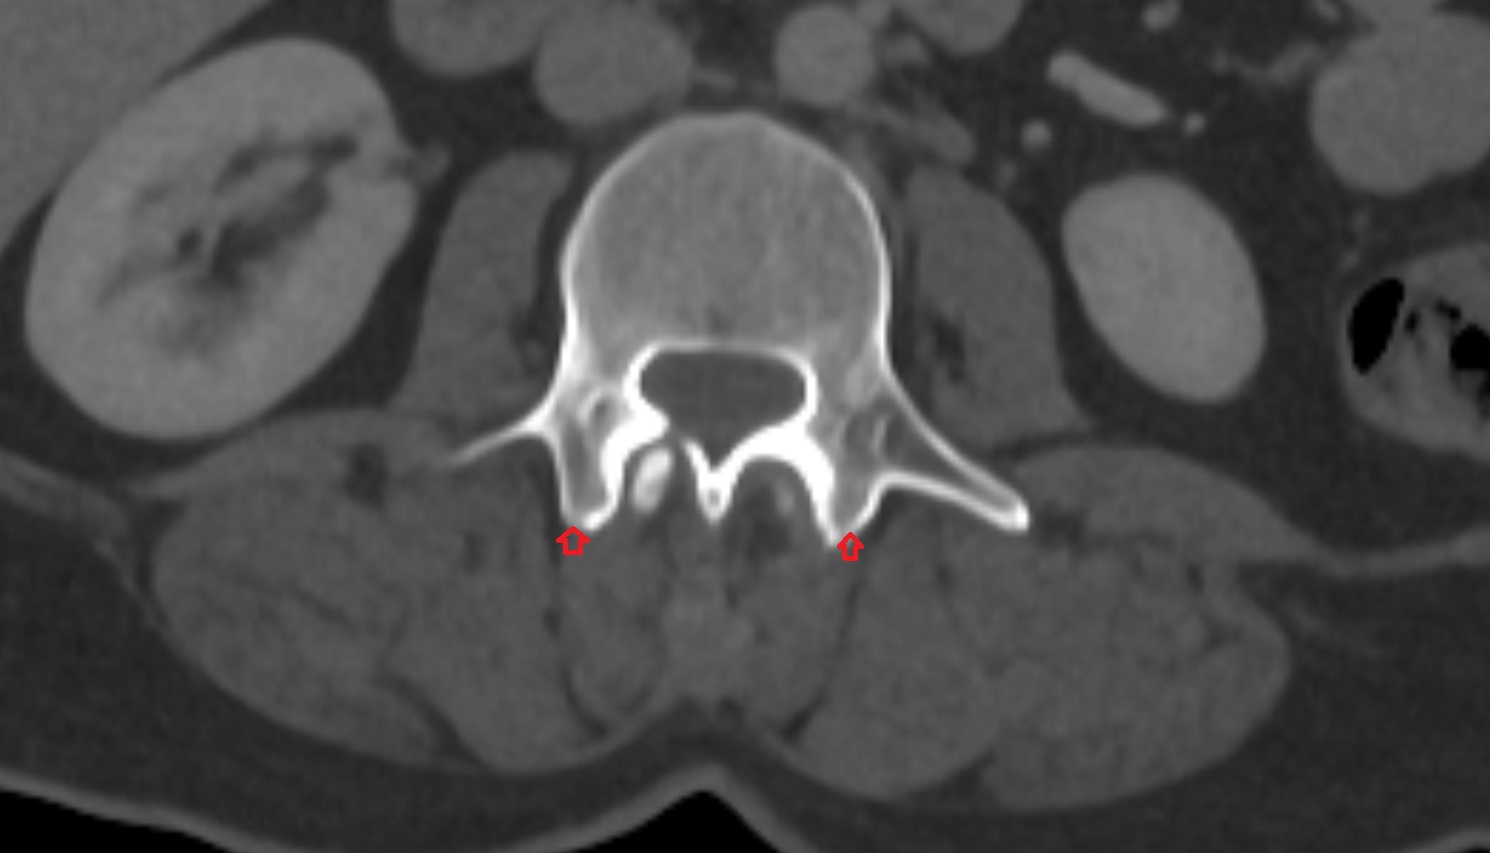

- Exit foramina